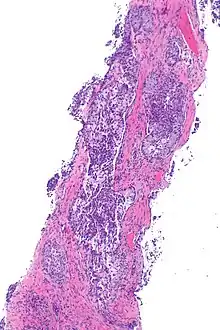

Micrograph showing ALK positive lung adenocarcinoma. H&E stain. | |

Most lung carcinomas containing the ALK gene fusion are adenocarcinomas.